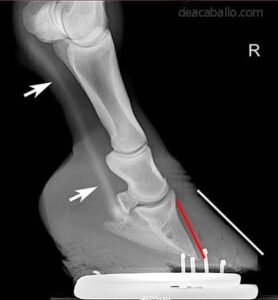

La laminitis equina, también conocida comúnmente como infosura, es una de las enfermedades más dolorosas, graves y potencialmente devastadoras que pueden afectar a los caballos. Consiste en la inflamación y a su vez una disminución del flujo sanguíneo causando el debilitamiento de las láminas, que son los tejidos blandos que actúan conectando el hueso tejuelo (tercera falange) con la pared interna del casco.

- Soporte del casco y reposo estricto: Confinamiento en una cuadra con una cama muy profunda y suave (arena o viruta) y uso de herrajes ortopédicos o botas especiales para dar soporte al hueso y aliviar la tensión.